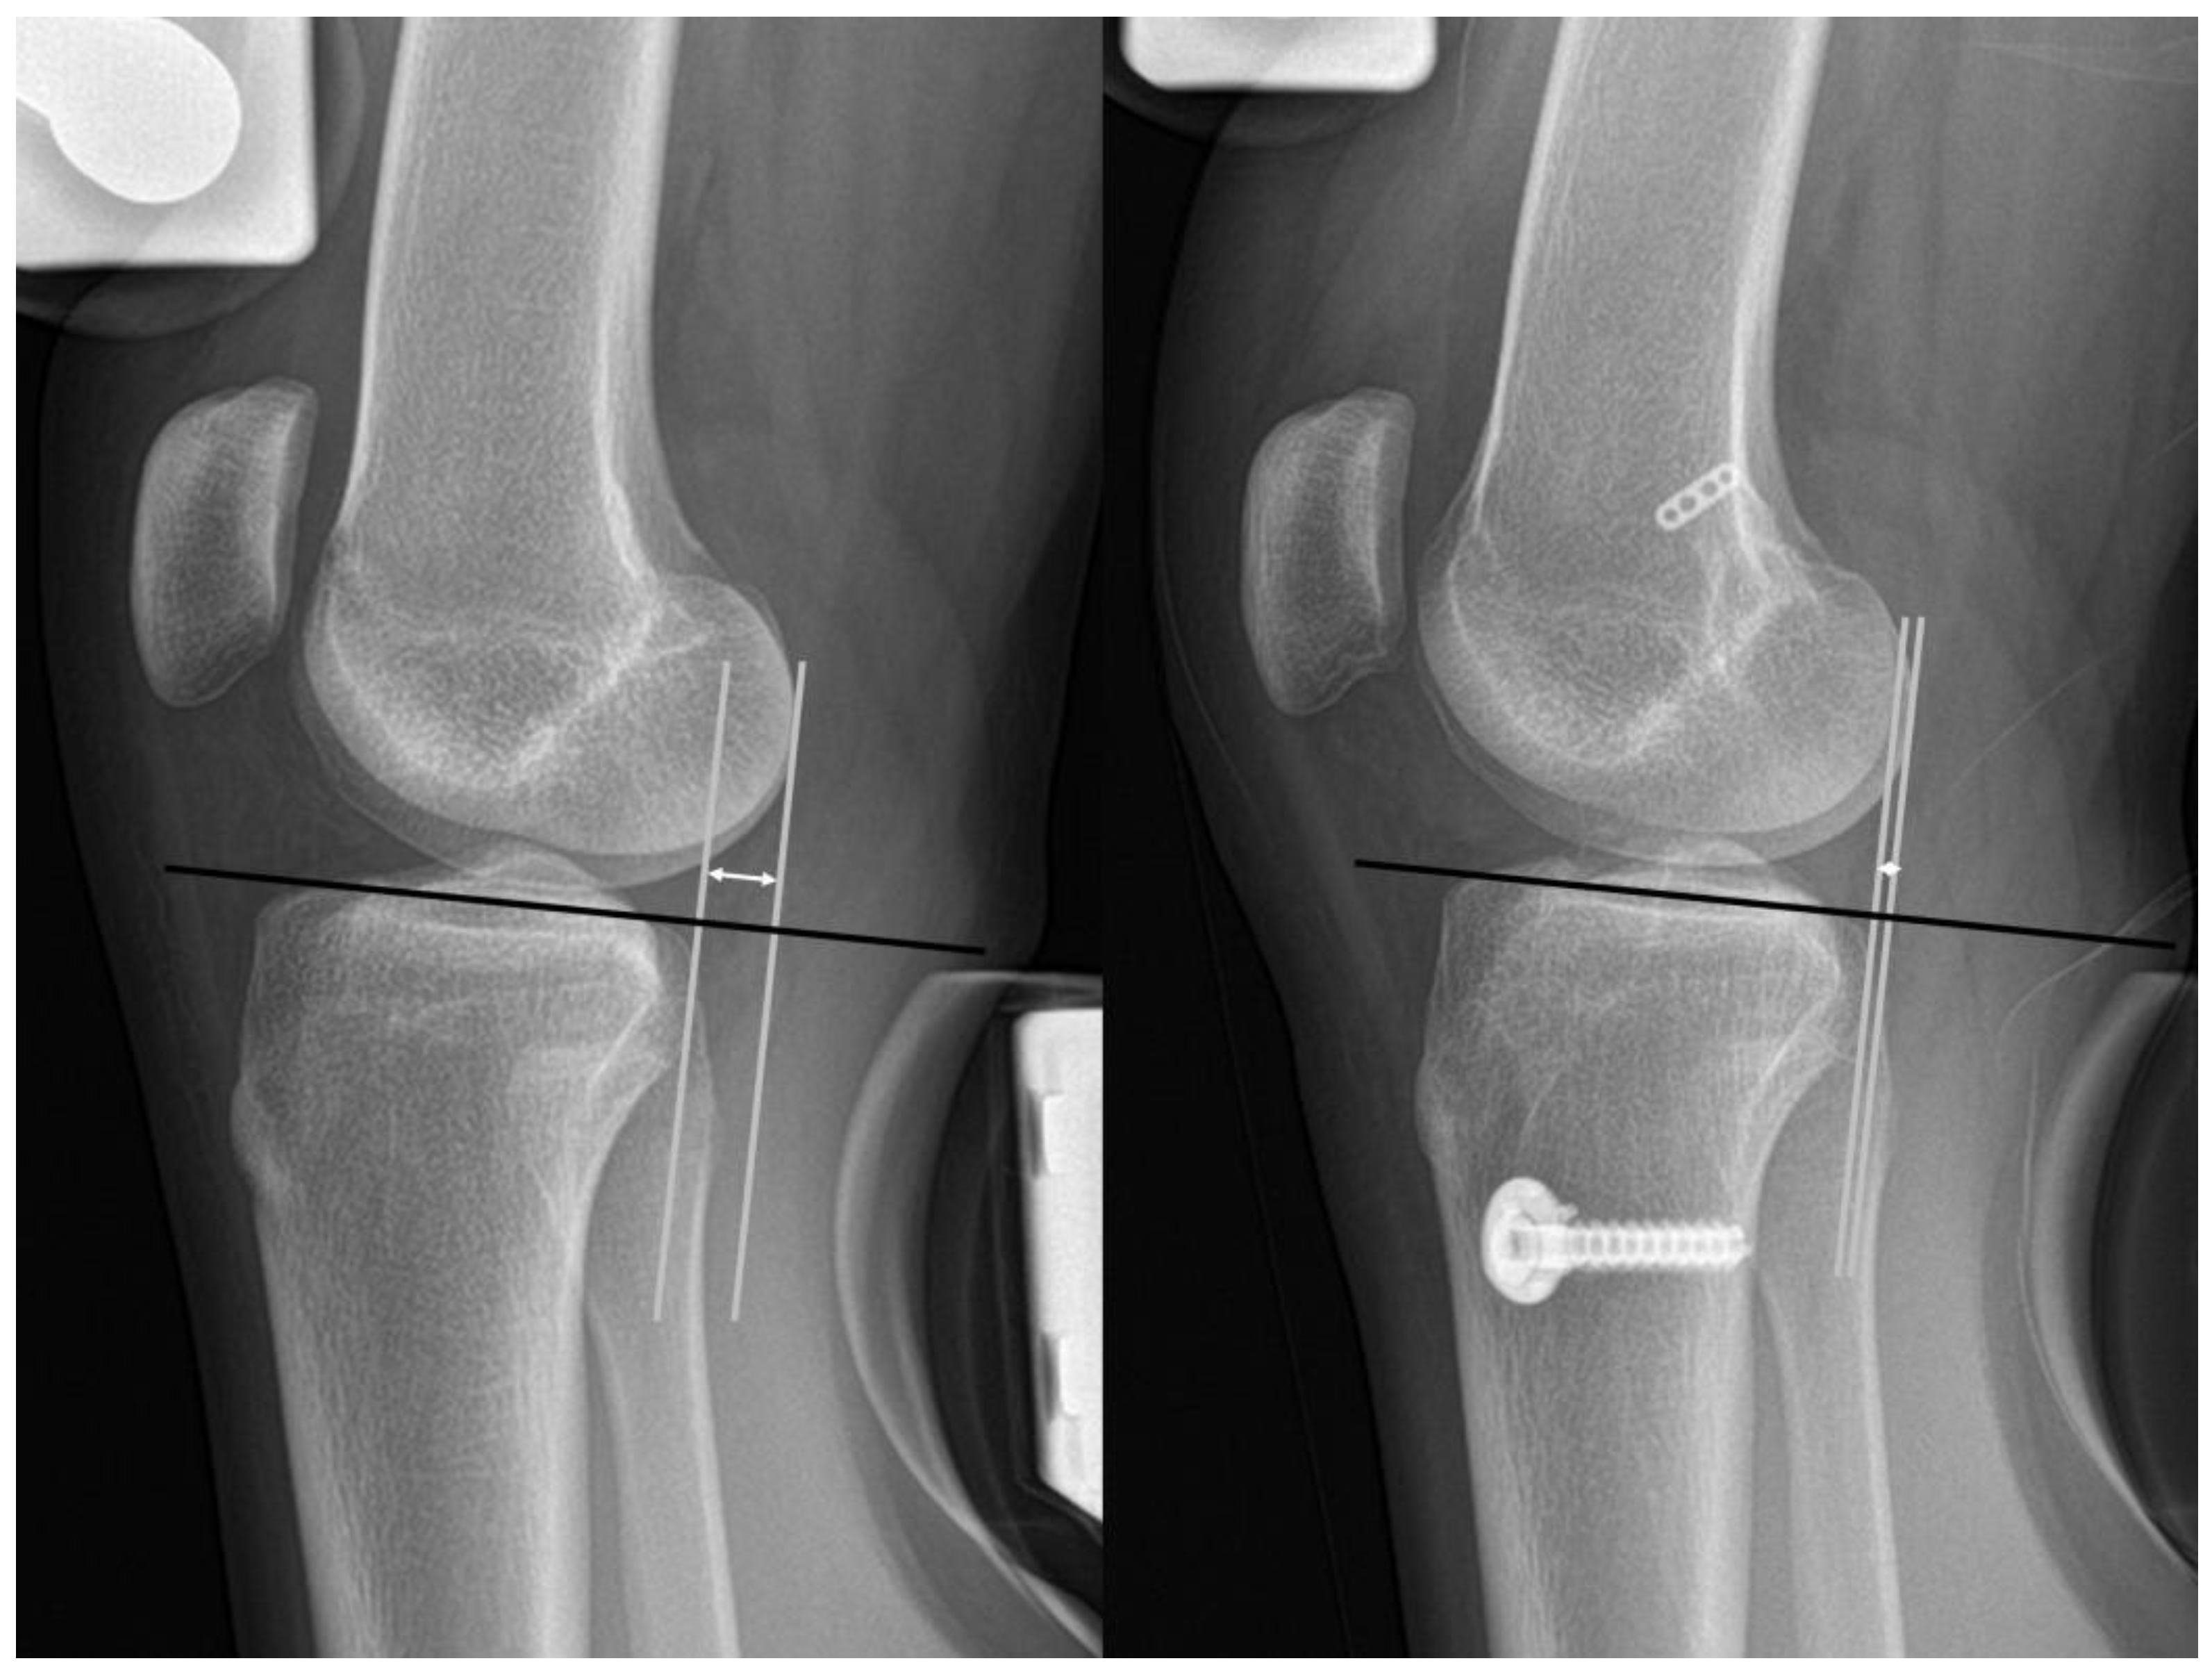

Postoperative plain radiographic outcomes were obtained from 2-year follow-up data. The preoperative hip-knee-ankle (HKA) angle was measured as the angle subtended by a line drawn from the center of the femoral head to the center of the knee, and a line drawn from the center of the knee to the center of the talus on whole-leg standing radiographs, with a positive and negative HKA angle indicating varus and valgus, respectively [33,34]. The tibial slope was measured as the angle between the mid-diaphysis line of the tibia and the line depicting the posterior inclination of the tibial plateau in the lateral view [35]. Anteroposterior knee joint stability was assessed using Telos Stress radiographs [36] (Figure 3). Preoperative and postoperative Telos Stress radiography (150 N on the tibia at 20–30° of knee flexion) was evaluated. A reference line was drawn parallel to the medial tibial plateau joint. The perpendicular lines from the reference line were drawn tangentially to the most posterior contour of the femoral condyle and the most posterior contour of the tibial plateau. The distance between the two lines was defined as anterior tibial translation. The side-to-side difference (STSD) was calculated to analyze native laxity, defined as the difference in anterior tibial translation between the knees. The STSD was measured preoperatively and at 2 years postoperatively, and the results were compared between each other.

Figure 3.

Measurement of pre- and postoperative anterior tibial translation on Telos stress radiographs. A reference line (black line) was drawn parallel to the tibial plateau joint line. Perpendicular lines (white lines) from the reference line were drawn tangentially to the most posterior contour of the femoral condyle and tibial plateau. The anterior tibial translation was defined as the distance between two lines (arrow line).